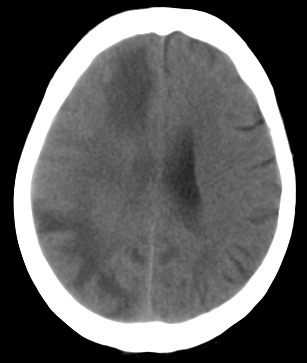

周*,女,78岁,阵发性意识障碍月余,查体四肢肌张力可,病理反射未引出。有脑哽塞病史

右颞顶枕叶多发低密度影,同侧脑室受压变形,病变有明显占位效应.考虑脑肿瘤性病变,建议增强!!!

影像表现: 右侧额、颞、顶叶多发等、低密度区,部分呈结节灶,灶周有不同程度水肿,散在发生,占位效应较重,感觉不是一个整体性病灶,病灶形态呈不规则状明显不同于mca供血区梗死,病变累及基底节区白质。

诊断:右侧额、颞、顶叶肿瘤性病变,首先考虑转移瘤。建议胸片。需与胶质瘤、mca供血区梗死以及脱髓鞘改变区别。

右侧颞,顶叶水肿呈指状,右额叶可见条形低密度带,右侧脑室明显受压,支持右侧脑实质多发转移瘤,建议增强,或拍胸部x片。

右颞顶枕叶多发低密度影,同侧脑室受压变形,病变有明显占位效应,建议增强.

病灶周围脑实质受压明显,右侧脑室受压变形,脑沟明显变浅。支持脑内肿瘤的第一诊断,(不知病人曾经的脑梗塞是否诊断明确),其次考虑脑梗塞的诊断(看起来不大像)

病史:女,78岁,阵发性意识障碍月余,查体四肢肌张力可,病理反射未引出。可基本除外缺血性病变。[br]影像表现: 右侧额、颞、顶叶多发等、低密度区,部分呈结节灶,灶周有不同程度水肿,散在发生,占位效应较重,感觉不是一个整体性病灶,病灶形态呈不规则状明显不同于mca供血区梗死,病变累及基底节区白质。[br]诊断:右侧额、颞、顶叶肿瘤性病变,首先考虑转移瘤。建议胸片。需与胶质瘤、mca供血区梗死以及脱髓鞘改变区别。

右侧额叶大片状水肿,呈指状改变,周围脑沟脑裂消失,右侧脑室受压缩小,提示占位效应明显,平扫未见明显瘤体,单纯从ct片上看可考虑肿瘤,转移瘤或胶质瘤,建议mri检查,以明确诊断.

右侧额、颞、顶叶多发不同程度低密度水肿区,可见占位效应

首先考虑右侧额、颞、顶叶肿瘤性病变,转移瘤可能性大。(部分病灶可能是梗塞性改变)